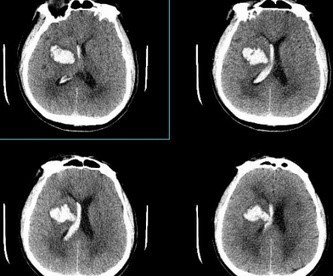

고혈압성 뇌출혈은 뇌혈관이 터져 뇌 조직에 출혈하는 응급 상황입니다. 고혈압 환자에게서 흔히 발생하며, 빠른 진단과 치료가 중요합니다. 치료가 지연되거나 적절하지 않을 경우 사망이나 심각한 장애를 초래할 수 있습니다.